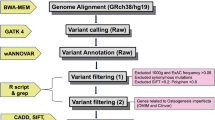

Libraries were prepared for sequencing on Illumina HiSeqX (Illumina Inc., San Diego, CA, USA) from the genomic DNA using the Illumina TruSeq DNA PCR-Free kit with a mean insert size of 400 bp. On average, this resulted in approximately 480 million mapped unique sequences with a mean coverage of > 37, i.e., 30x coverage for 80% of reference sequences. We used an in-house pipeline developed by the Science for Life Laboratory, Stockholm, Sweden to map reads to the human reference genome (hg19) and to call variants. Data were aligned to the reference genome using bwa (v0.7.12) [27].

We deduplicated, recalibrated, and indel realigned raw alignments using GATK (v3.3–0-geee94ec) [28]. The quality control information was gathered using Qualimap (v2.2) [29] and single-nucleotide variants (SNVs) and indels were called using the HaplotypeCaller in GATK. Supplementary Table 1 presents general statistics of WGS data to show sequencing quality. We further processed the variants with GenotypeGVCFs, VariantRecalibrator, ApplyRecalibration, VariantFiltration and SelectVariants tools in GATK (v3.7), which were then functionally annotated using Variant Effect Predictor (VEP; version 89) [30] and loaded into a database using GEMINI (v0.20.0) [31]. We followed two approaches. We excluded variants with minor allele frequency of 0.1% and higher in 1000 Genomes Project (1000G), 6500 NHLBI-GO Exome Sequencing Project (ESP), Swedish Genome Project (SweGen) [32] and Exome and Genome Aggregation Consortium (ExAC and gnomAD). Variants located in repetitive sequence regions were excluded. Only non-synonymous variants, frameshift indels, and putative splice site variants were considered for further analysis. We used Combined Annotation Dependent Depletion (CADD) to score the pathogenicity of SNVs [33]. Evolutionary conservation of variants was evaluated with Genomic Evolutionary Rate Profiling (GERP) [34]. The variants were explored in the database using built-in tools in GEMINI, and variants were visualized on Integrated Genome Viewer (IGV) [35].

Structural variants were analyzed using the FindSV pipeline (https://github.com/J35P312/FindSV) which merges calls from CNVnator V0.3.2 [36] and TIDDIT [37]. The structural variants were annotated by VEP and filtered based on the quality flag of the variant. The filtered and annotated variants were then sorted based on a local structural variant frequency database consisting of variants from 1000 healthy individuals from the SweGen project. The reads at breakpoints were visualized in the IGV. The structural variants that fall into intergenic regions as well as intronic deletions and duplications were excluded.

Based on literature reviews, in a systematic manner, we created a panel of genes that are associated with nonsyndromic and syndromic hypodontia or oligodontia as well as of genes involved in tooth development in animal models [8, 38, 39] (Supplementary Table 2). In our downstream analysis of the whole-genome sequencing (WGS) data, we also used this gene panel to investigate both single nucleotide and structural variants in genes that have roles in tooth agenesis and tooth development. Here, we applied a minor allele frequency higher than 1% for the population databases to filter out common single nucleotide variants. In the structural variant analysis, we focused only on breakpoints located in the exons of coding genes that were listed in our gene list (Supplementary Table 2).

Mean age at the most recent evaluation of dental phenotype in the 10 individuals was 12.8 ± 3.7 years (range 7.7–19.9 years). Missing premolars were the most frequent finding, 92% (61/66). The individuals included into this study presented with a heterozygous variant in COL1A1, 70% (7/10) and COL1A2 (3/10). The majority of COL1A1 and COL1A2 variants were de novo mutations (Table 1). Whole genome sequencing confirmed pathogenic COL1A1/A2 mutations in 9 of the 10 individuals. One boy (patient no. 6) previously diagnosed with OI type III had been diagnosed with a splice variant in COL1A1 (c.3208-6C > T). This variant was assessed as likely benign in this investigation since it is a common single-nucleotide polymorphism (SNP) (gnomAD v2.1 MAF: 0.00068) and we concluded that it was not responsible for the patient’s OI phenotype. However, we identified a homozygous nonsense variant in CREB3L1, p.Tyr428*, c.1284C > A (NM_052854.3) (Fig. 1a). At the time of analysis, this variant was not found in any publicly available population database but is recently published [40]. It creates a stop codon, resulting in a premature termination of protein at position 428 instead of 519. The CADD score was very high (36.0) and Tyr428 is evolutionarily conserved across species (Fig. 1b). The mutation was located on the C-terminal of OASIS which is localized in the rough endoplasmic reticulum. Based on the literature, it was assessed as the most likely disease-causing variant, and we discarded the COL1A1 variant.

The CREB3L1 variant visualized on an Integrated Genome Viewer (IGV) and schematic representation of the domain structures of human OASIS. (a) The homozygous variant at chr11(hg19): 46341840 C > A in whole genome sequencing data on IGV in patient no 6. The variant is located in CREB3L1. It creates a stop codon at position 428 and causes early termination of the protein (p.Tyr428*, c.1284C > A). (b) Schematic representation of the domain structures of human OASIS. Different domains are colored in different shades of grey. Mutations identified in this study (p.Tyr428*) and identified by Keller et al. (p.Lys312del) have been shown on the protein. The mutation is located directly after the S1P recognition motif (RSLL), highlighted in grey. Multiple sequence alignment shows evolutionary conservation of Tyr428 across species